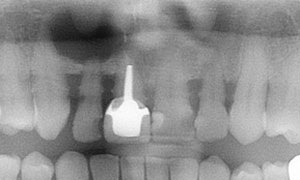

L’incisive centrale droite est mobile et disgracieuse. Les dents voisines du patient sont colorées et porteuses d’anciennes résines.

L’incisive latérale droite est porteuse d’un kyste important. Une maladie parodontale chronique généralisée génère des mobilités dentaires et des saignements gingivaux.

Le traitement parodontal non chirurgical a stabilisé la maladie parodontale et a permis la pose de deux implants en sites de deux incisives et de facettes sur les dents voisines.

Le patient a retrouvé l’esthétique de son sourire et le confort.